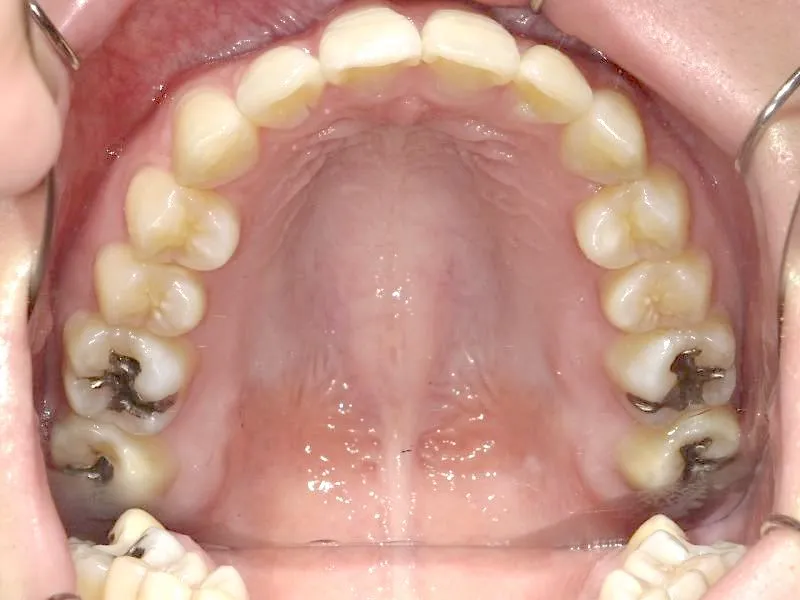

奥歯が内側と前方にかたむき上下の歯がガタガタに生えています。

90度ねじれた歯もあります。前歯も出っ歯になっています。

歯は抜かず、歯科矯正用アンカースクリューを用いて治療しました。

治療回数○回、2年9ヶ月の治療期間で矯正治療を終了しました。

主訴が改善され、ご満足頂きました。